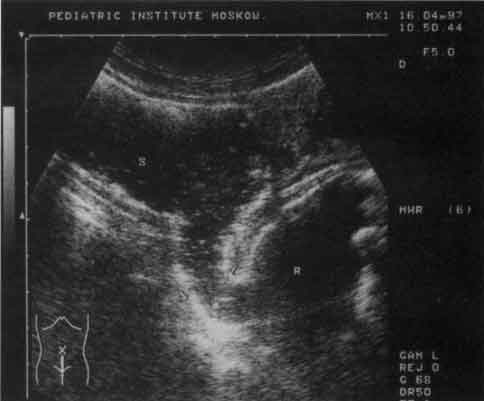

Рис. 10. Эхограмма прямой (R) и сигмовидной (S) кишки (продольный срез). В просвете прямой - полип (обозначен стрелкой).

Рис. 11. Эхограмма прямой (R) и сигмовидной (S) кишки при болезни Гиршпрунга.